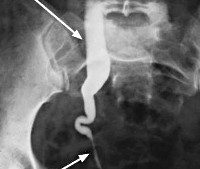

• Инструментальные методы. УЗИ почек, мочевого пузыря, ТРУЗ с контролем остаточной мочи являются основными диагностическими методами, направленными на выявление причин возникновения гидроуретанов. Экскреторная урография не проводится при хронической почечной недостаточности. После получения смешанных результатов проводится КТ и МРТ. Эти процедуры предпочтительны для определения опухоли забрюшинного пространства, сдавливающей мочеточник; нет никакой разницы с увеличением креатинина. По показаниям проводится ренография, уретеропиелоскопия, нисходящая цистография, КУД.

ИРП ОБП и забрюшинное пространство. Выраженное стойкое расширение мочеточников с обеих сторон.